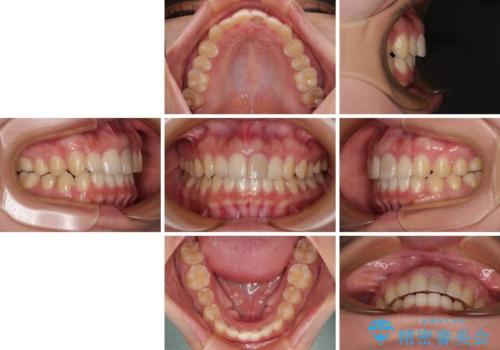

飛び出した上顎前歯 インビザラインで引っ込める

- 前歯の突出感を気にして来院された患者様です。

奥歯の咬み合わせは理想的な咬合に近く、インビザラインでも十分に対応できる歯列でした。

舌の突出癖を改善するためのトレーニングを行いつつ、上下歯列全体を後方に移動させ、更にはIPR(歯と歯の間を削る)によりスペースを獲得することで、口元の突出感を改善することとしました。

治療途中に上顎前歯が歯髄壊死を起こし、変色してしまいました。

痛みを感じたらすぐに連絡いただくよう伝えていましたが、忘れてしまっており、痛みと変色が発現したことで、すぐに連絡することを思い出されたとのことでした。

今後は、根管治療を行った後に、オールセラミッククラウンにて補綴治療を行う予定です。